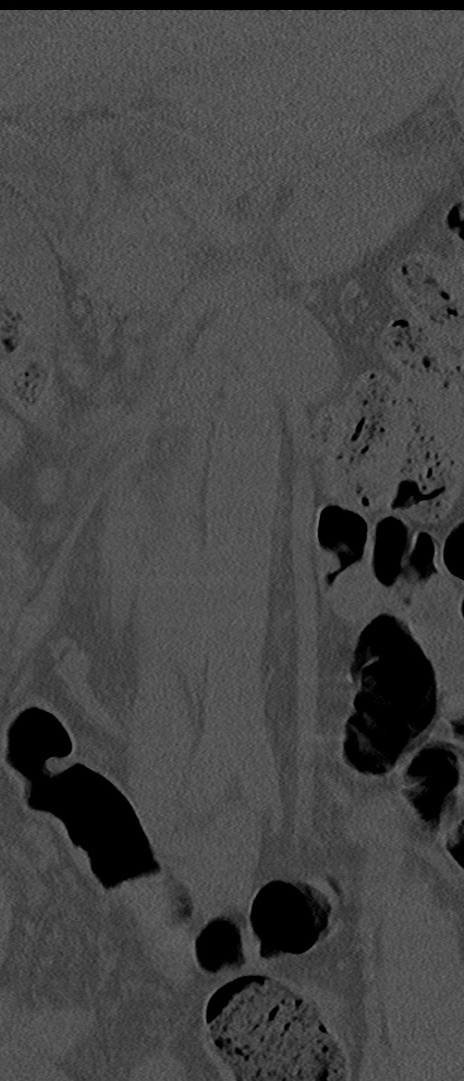

【整形】TIPS症例4 腰椎CT(冠状断像)

腰椎CT